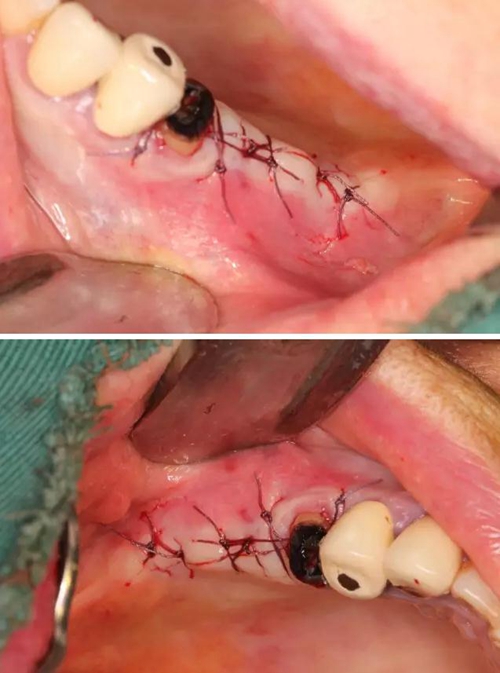

【病例分享】右上內(nèi)提+5冠延長(zhǎng)1 梁光強(qiáng)